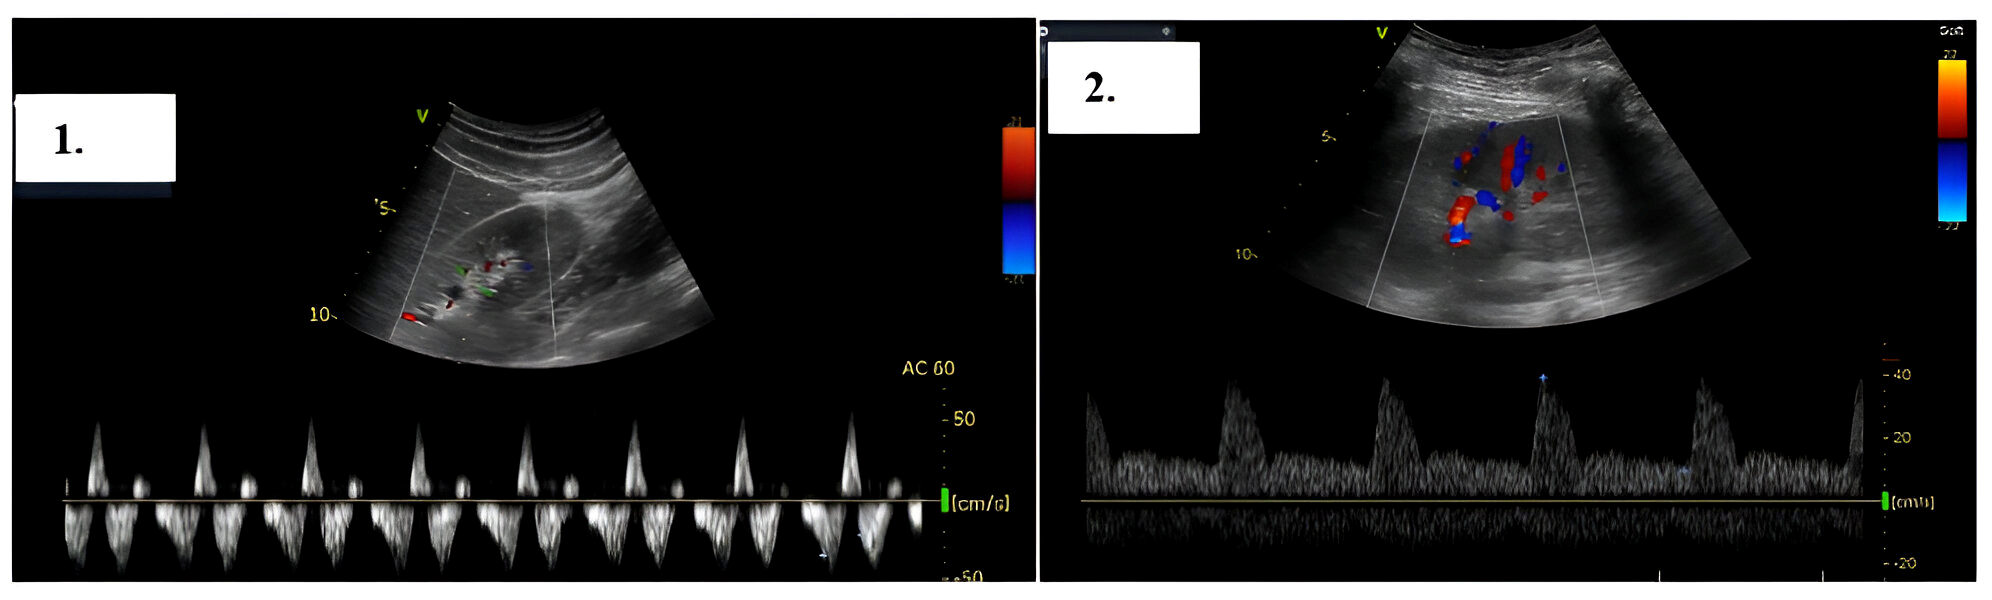

2. Case Presentation

- Grigore, M.; Grigore, A.M.; Ilieșiu, A.M. Portal Vein Pulsatility: A Valuable Approach for Monitoring Venous Congestion and Prognostic Evaluation in Acute Decompensated Heart Failure. Diagnostics 2024, 14, 2029. [Google Scholar] [CrossRef] [PubMed] [PubMed Central]